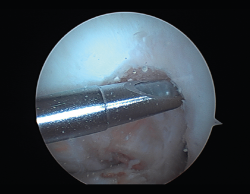

Las principales causas secundarias a errores técnicos son la malposición de la plastia y el tensado excesivo. La radiografía permite ver la localización de los túneles e implantes, así como la RM visualiza las partes blandas implicadas, pudiendo identificar posibles pinzamientos de la plastia –escotadura intercondílea, síndrome del cíclope (Figura 9), síndrome de la contractura infrapatelar(22) (Figura 10)–.

Figura 9. Cíclope, tejido fibroso interpuesto en la cara anterior de la plastia y que produce pinzamiento de la misma en extensión de rodilla.